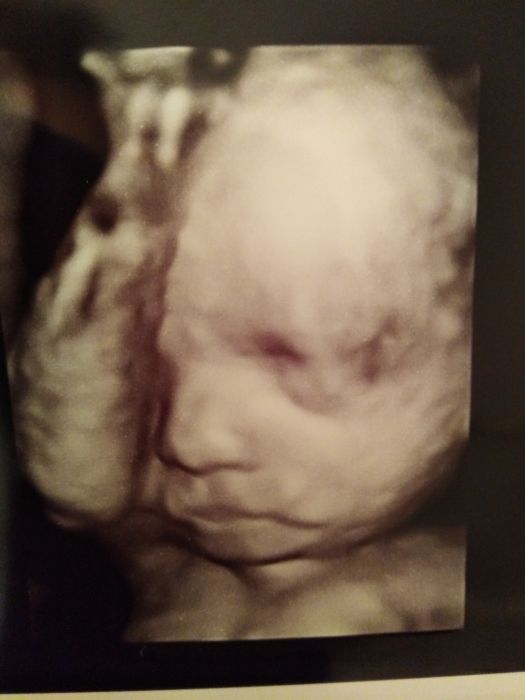

Ahoj holky, na včerejší nečekaně kontrole kvůli tomu, že mě pustili v pondělí že špitálu po ledvinove kolice plus včera mi dělali 3D,dopadla dobře, sice malej nechtěl moc spolupracovat, furt spal ruce před sebe ? Malej má přes 1100g o okolo 35cm ? tak snad se nenarodil nějaké buřtik ? Jinak sme v pořádku, čípek je ještě dlouhé, tak snad ještě vydrží 3 měsíce ?